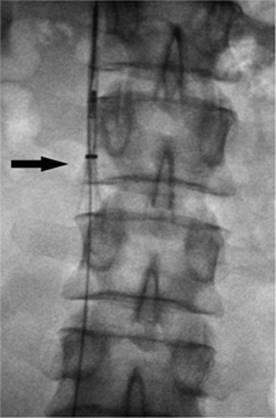

Figure 35.23. Attempted canalization of the portal vein during a transjugular intrahepatic, portacaval shunting (TIPS) procedure. The tip of the cannula is in the renal pelvis (black arrow).